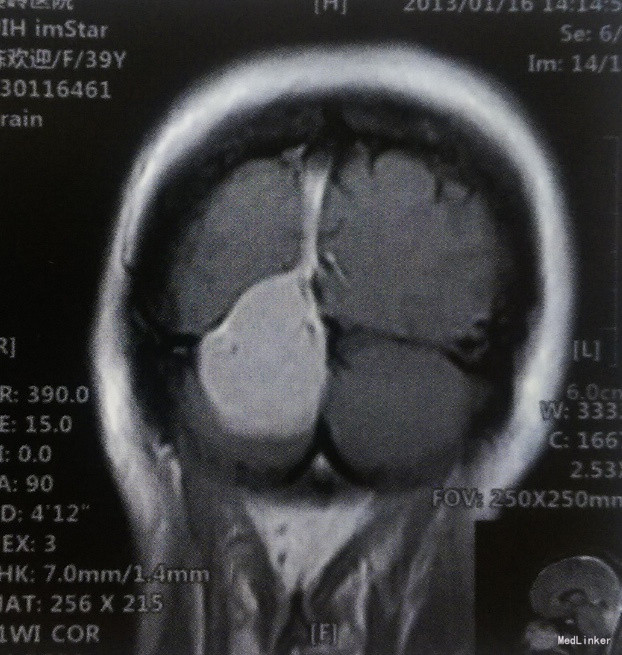

患者,女,39岁,已婚。主因间断头痛、头晕1年,加重1个月入院。 患者于1年前无诱因偶发头痛,以左颞部为著,呈钝痛,伴头晕,夜间休息时明显,打喷嚏时加重,自行口服“止痛药”效果不佳。1个月前上述症状加重,双颞侧头部闷痛明显,前往当地医院就诊,行头颅MRI检查:小脑幕下右侧小脑半球后方占位性病变,考虑脑膜瘤。未行任何治疗,门诊以“右侧小脑幕脑膜瘤”收入我科。既往体健,无其他相关病史。

体格检查:神经系统查体未见明显阳性体征。 术前影像学检查 头颅MRI检查:肿瘤边界清楚,T1WI呈等信号,T2WI为略高信号,信号均匀,病灶呈宽基底,与小脑幕及颅骨内板相连,增强扫描均匀强化,可见,“脑膜尾征”。

诊断:右侧小脑幕上下巨大脑膜瘤 治疗:手术切除